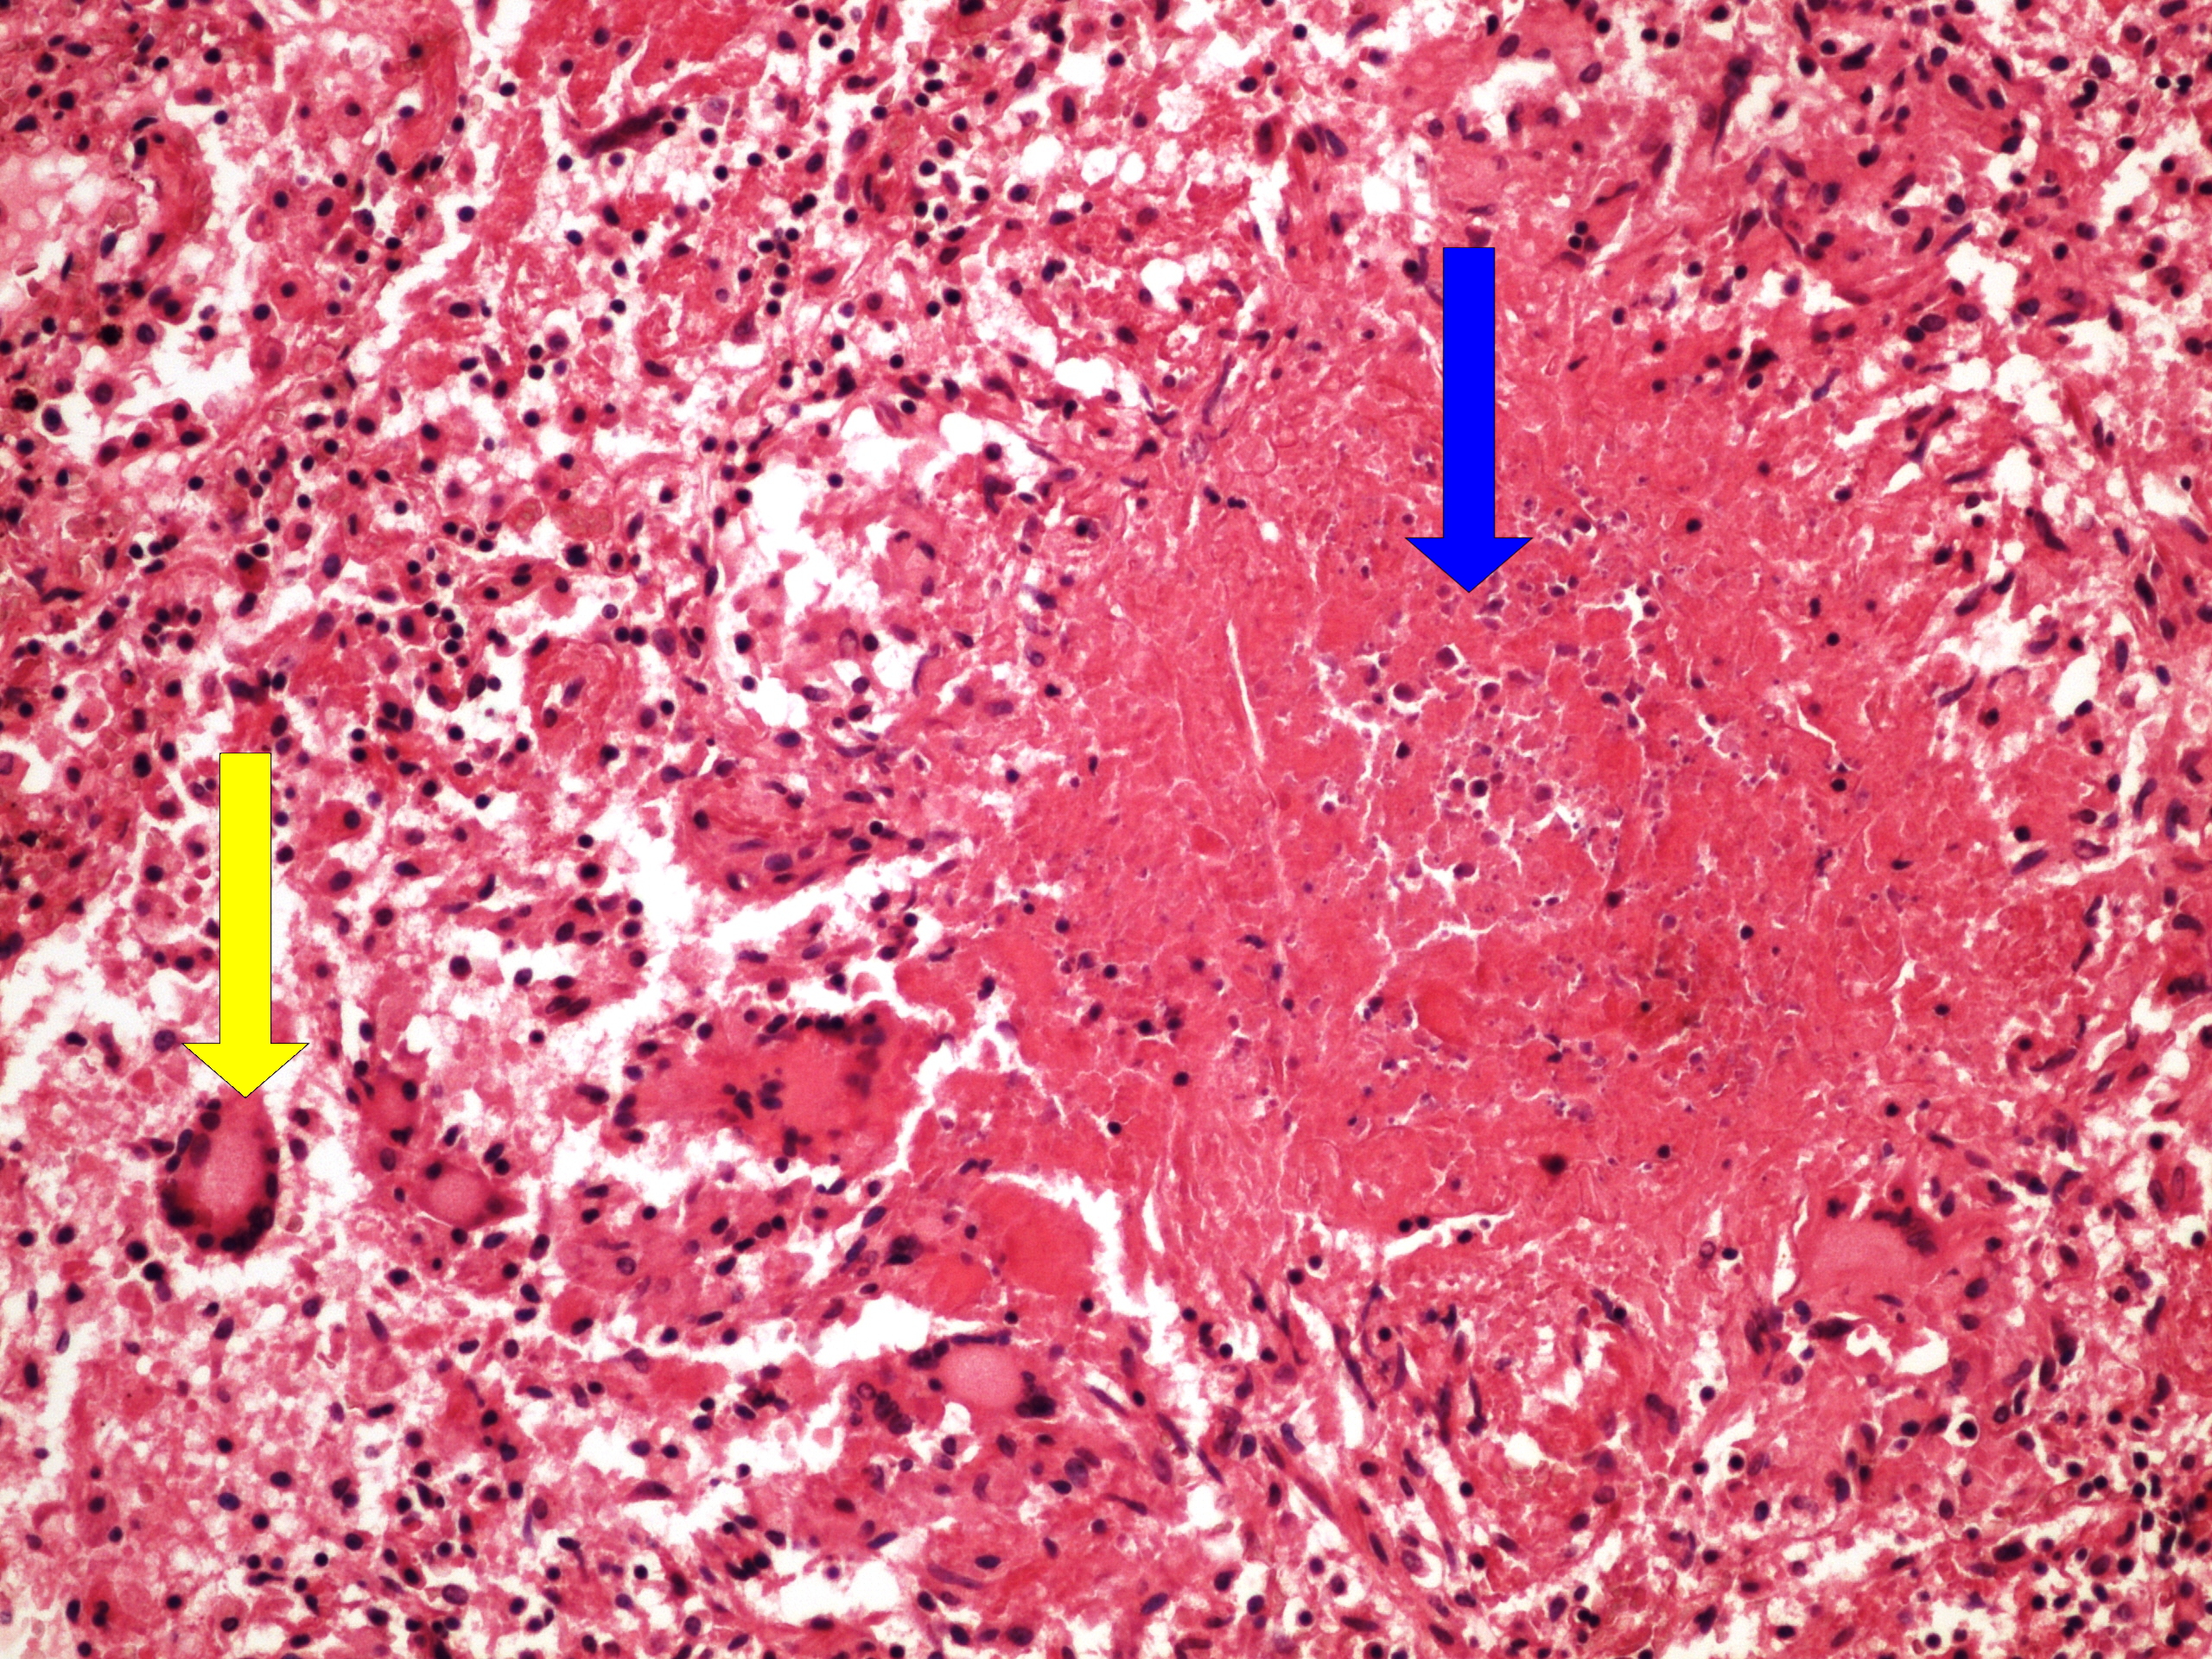

Preparát č.23 a č.24 - miliární TBC plic

Struktury

- miliární uzlík

- vícejaderné buňky Langhansova typu